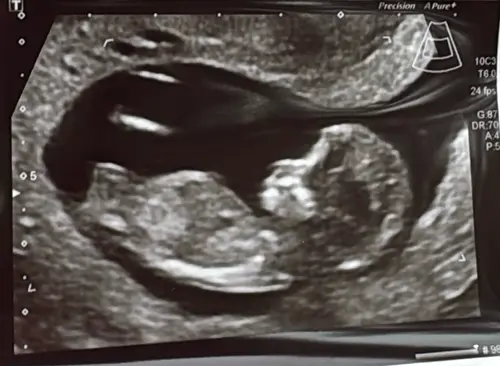

Jongen of meisje? 🩷🩵 13 weken vandaag

Hij of zij ligt zo in een kommetje. Ik vind het lastig om te zien. Is iemand hier misschien heel goed in hihi.